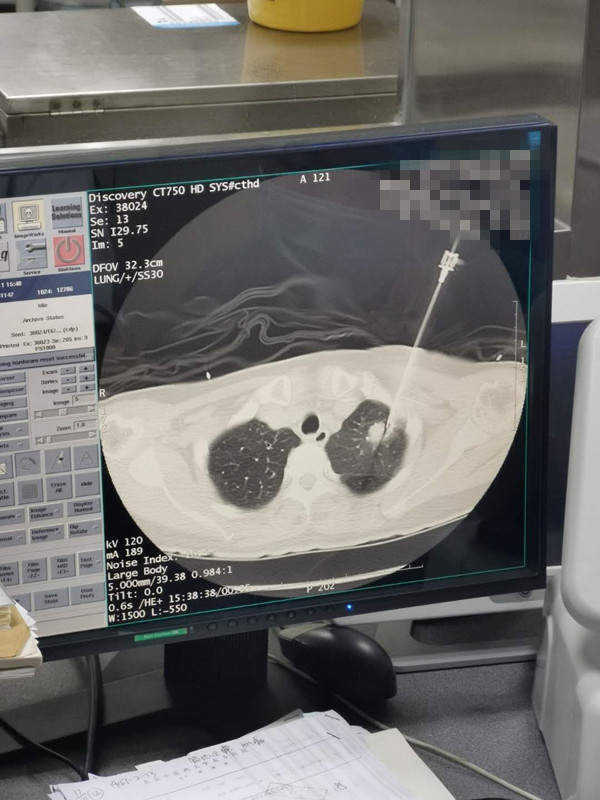

66岁肺部氩氦刀冷冻消融

发布人:美国氩氦刀技术官方网站    发布时间:2020/8/12 16:28:51